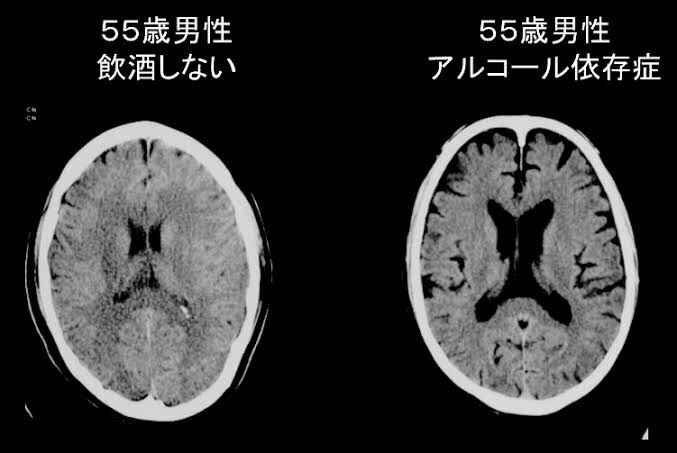

40 : 雑ニュー :2025/02/07(金) 19:08:51 ID:X6LH3hpF0

アル中脳